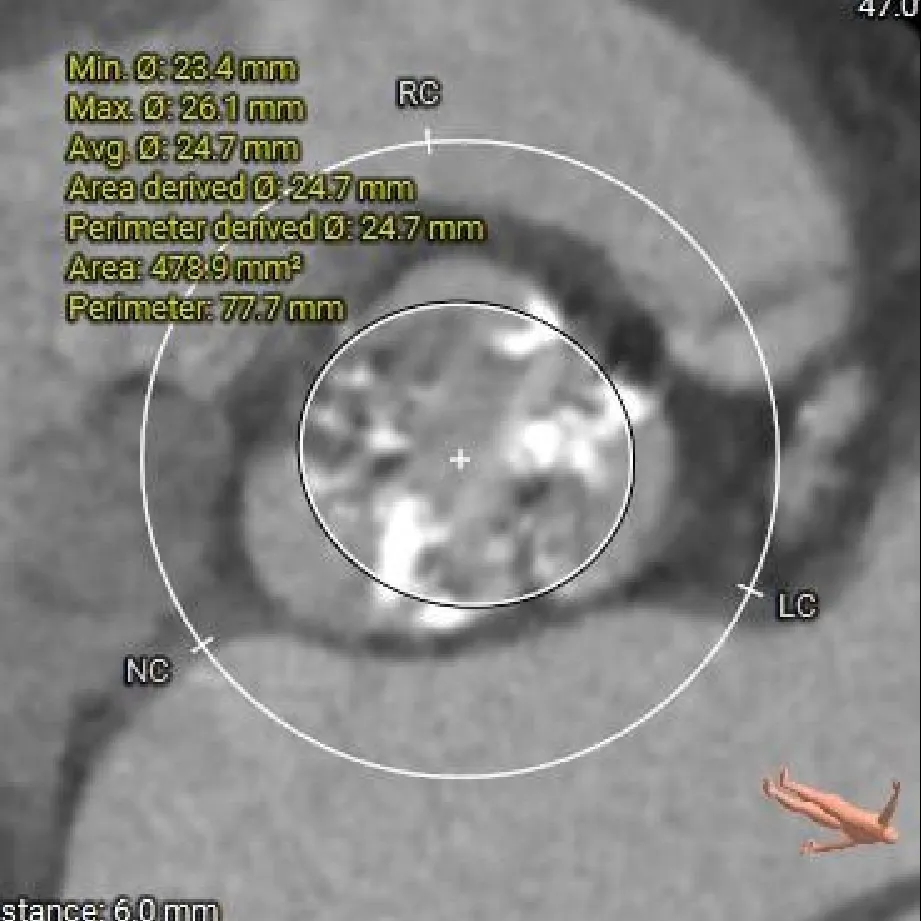

瓣上 6mm

24.7mm